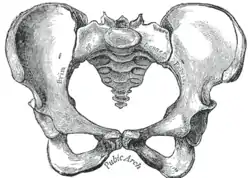

Male pelvis |

Female pelvis |

Top: Stylised illustration of humans on the Pioneer plaque, showing both male (left) and female (right).